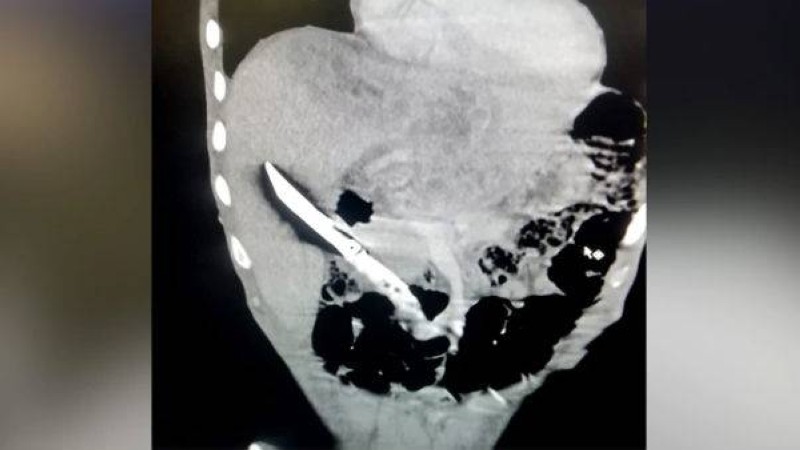

وكشفت الموجات فوق الصوتية والأشعة السينية للبطن شفرة سكين مطبخ عالقة في الكبد، كما أنها تسببت في نتوءات وتعفن في الدم.